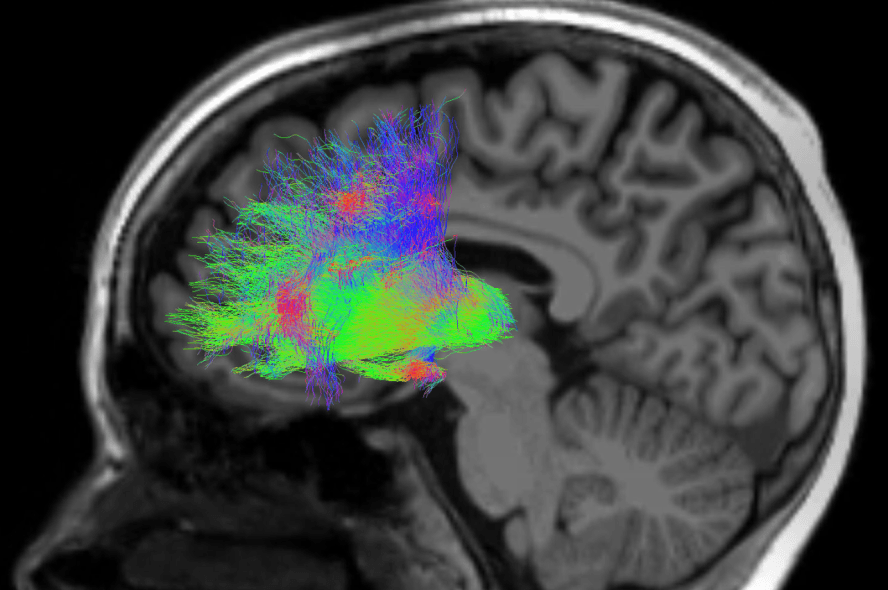

CCK basket cells are involved in inhibitory neuronal pathways that are involved in functions like mood regulation and working memory. In primates, activating cannabinoid 1 receptor (CB1R) G-protein coupled receptors in the prefrontal cortex by Δ9-tetrahydrocannabinol (THC) had a detrimental effect on working memory, and CB1Rs are almost exclusively expressed by CCK basket cells. Since previous research demonstrates that dysfunctional basket cells and impaired memory likely play a role in schizophrenia, researchers suggest that marijuana use is an interactive risk factor or mechanism for increased vulnerability to schizophrenia.